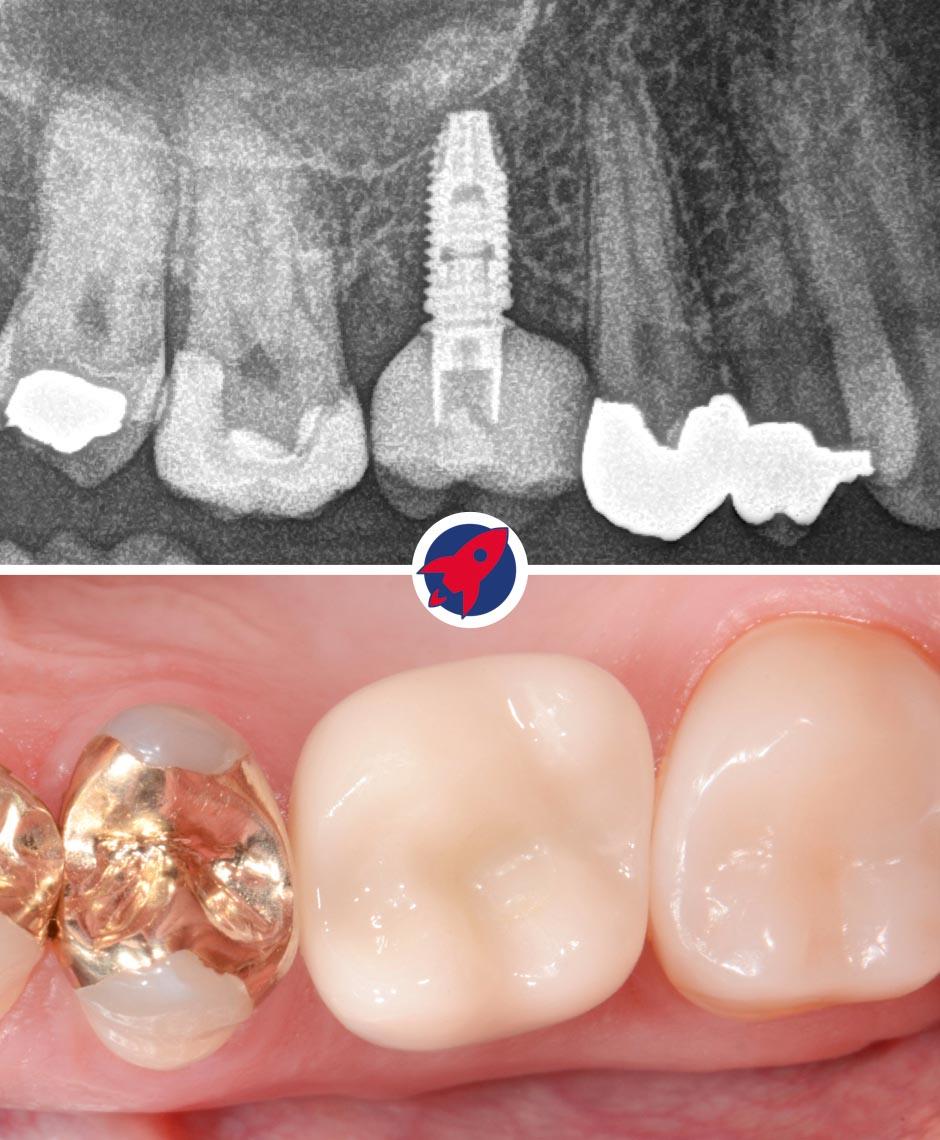

Above, you can see an X-ray image showing the implant with the dental crown attached. Below, the crown is shown in a clinical view in the mouth.

Endgültige Ansicht eines Zahnimplantats mit Krone: Hier ist das finale Ergebnis einer Implantatbehandlung zu sehen, bei dem das Implantat vollständig im Kiefer integriert ist und mit einer individuell angefertigten Zahnkrone abgeschlossen wird, die sich nahtlos in die natürliche Zahnreihe einfügt.